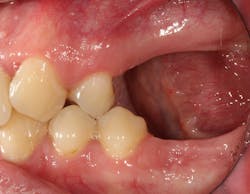

These alveolar bone changes often compromise implant placement due to thin bone volume (figures 2a–2d).

Reduction in quantity and quality of bone can also compromise functional and esthetic outcomes of both implants and fixed bridge restorations (figures 3 and 3a).